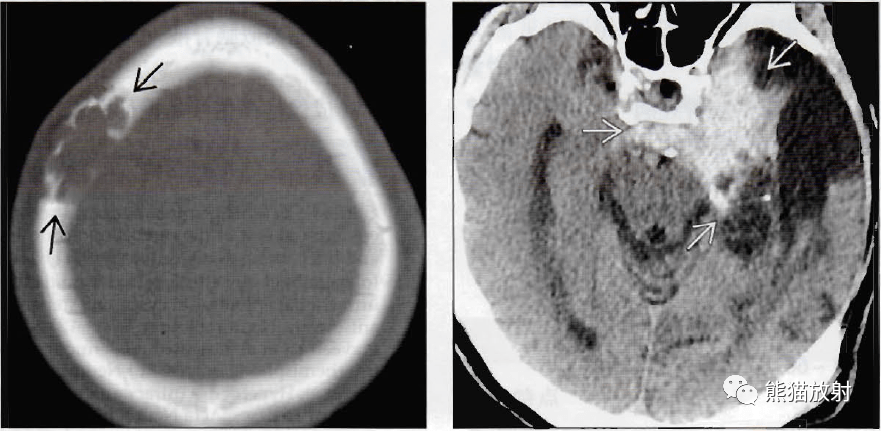

(左)轴位骨ct显示一例板障内表皮样囊肿的典型表现,病变外观呈膨胀性